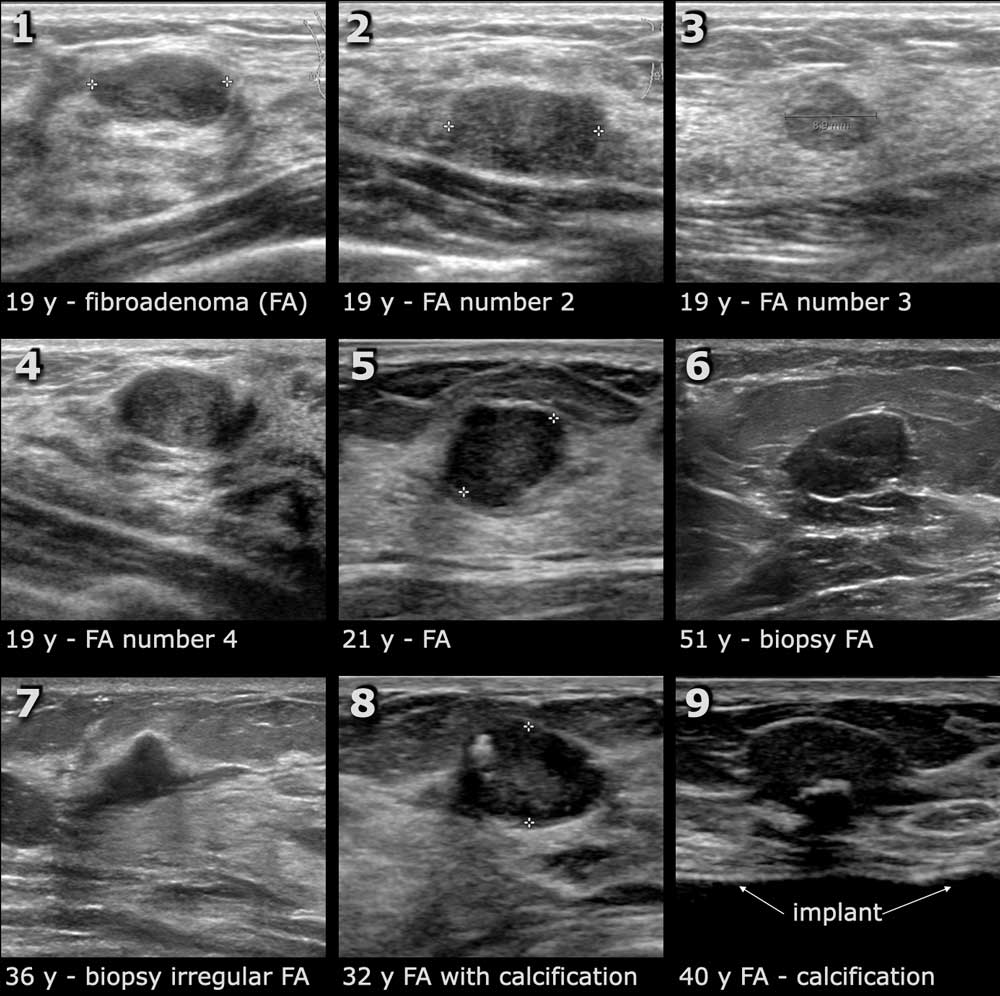

During a casual discussion with her friend, Meera, who worked in the healthcare sector, Ananya learned about breast ultrasound. Unlike the mammogram, which uses X-rays, breast ultrasound employs sound waves to produce images of the breast tissue. This method is particularly effective for women with dense breast tissue, offering a clearer and more accurate diagnosis without the discomfort of compression or exposure to radiation.

Meera explained that breast ultrasound could serve as a complementary tool to mammograms or as a standalone procedure for those at higher risk or with dense breast tissue. It was a revelation for Ananya — a practical solution to her ongoing dilemma.